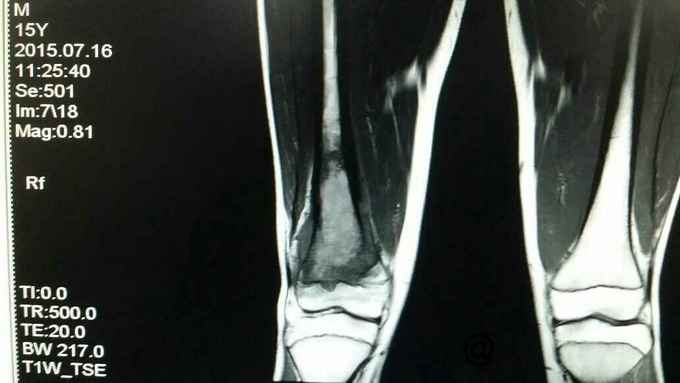

主诉:右大腿疼痛一月余 病史:患者一月前无明显诱因出现右大腿疼痛,未予诊治,自服消炎止痛药物治疗(具体不详),效差,至当地县医院DR示:右股骨远端占位,建议上级医院进一步诊治。

查体:右股骨远端一5cm×3cm大小质硬包块,压痛明显,周围皮温明显升高,患者疼痛拒绝活动。

完善术前各项检查,检验,穿刺活检回示:考虑骨肉瘤,参加省病理会诊及北京积水潭会诊回示:符合骨肉瘤,进行术前新辅助化疗,期间定制肿瘤假体,化疗2个周期后,患者复查磁共振,肿块明显缩小,行右股骨远端骨肉瘤肿瘤膝关节置换术。